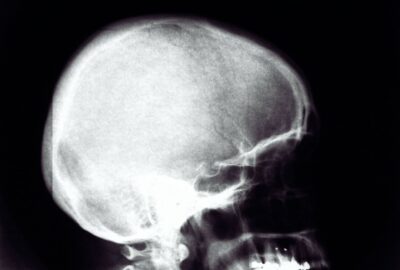

Kyste odontogène chez l’enfant : guide complet parents